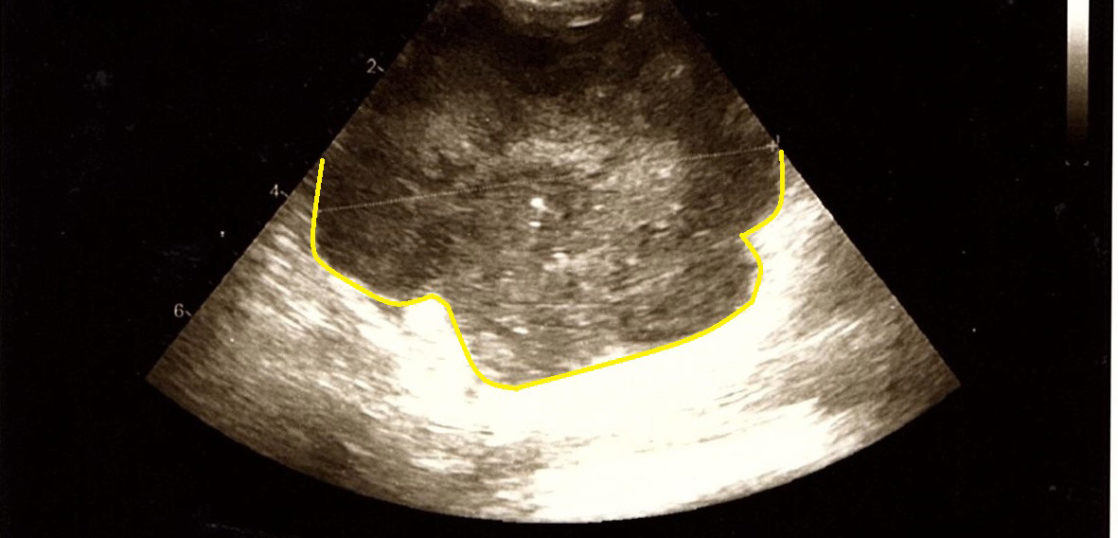

猫の脾臓腫瘍(リンパ腫もしくは肥満細胞腫)が縮小した使用例(エコー画像)

猫(23歳)の肥大した脾臓が縮小した症例です。リンパ腫もしくは肥満細胞腫が疑われています。

獣医師の触診で脾臓にボコッとした腫瘍がありましたが、現在は触れなくなり脾臓表面は滑らかです。(先生コメント)

コルディを服用して約50日という短期間で脾臓の腫瘍が触診で触れなくなり、コルディの効果を実感しました。

画像提供:つつじヶ丘動物病院

コルディ使用前(2013年9月29日)

コルディ使用後(2013年11月16日)